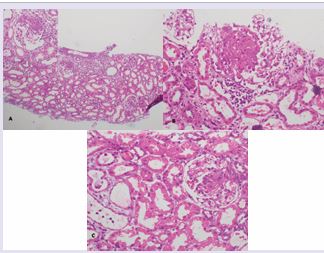

Figure A: Histopathological changes of case 1 to 3 represented by figures A to C (Haematoxylene and eosin stain). A) Low power view (X10) shows a focus of acute tubulo-interstitial inflammation and the inset shows (X40) segmental necrotizing glomerular lesion in

Case 1. B: Histopathological changes of case 1 to 3 represented by figures A to C (Haematoxylene and eosin stain). B) demonstrate (X40) segmental necrotizing glomerular lesions in cases 2 and 3 respectively. Histopathological changes of case 1 to 3 represented by figures A to C (Haematoxylene and eosin stain). A) Low power view (X10) shows a focus of acute tubulo-interstitial inflammation and the inset shows (X40) segmental necrotizing glomerular lesion in Case1. C) demonstrate (X40) segmental necrotizing glomerular lesions in cases 2 and 3 respectively.

An eight-year-old girl with steroid dependent, frequently relapsing nephrotic syndrome since the age of five years was commenced on levamisole (2.5 mg/kg on alternate days) as a steroid sparing agent, which was continued for three years. Her last relapse had occurred eleven months prior to presentation and she was on alternate day levamisole monotherapy when she presented with bilateral knee joint arthralgia and a skin rash over the lower limbs for one week duration. Examination revealed pallor and a purpuric rash on both lower limbs. Ear lobe lesions were not detected. There was no clinical evidence of arthritis or oedema detected. Blood pressure was 96/52 mmHg and the rest of the system examination was normal. Her haemoglobin (Hb) level was 9.8 g/dl with blood picture evidence of hypochromic microcytic anaemia. White blood count was 7.49x103/µL, platelets 775x106/µL. Erythrocyte sedimentation rate (ESR) was 98mm in the 1st hour. Serum creatinine remained normal during hospital stay (43 µmol/l). Urinalysis revealed albumin 1+ with moderately field full red cells. Normal complement C3 and C4 levels were noted with negative anti-nuclear antibodies (ANA) and anti-double stranded DNA antibodies (dsDNA). Perinuclear and cytoplasmic anti-neutrophil cytoplasm antibodies (pANCA and cANCA) were positive. Renal histopathology revealed focal segmental necrotizing glomerulonephritis in 3 out of 18 glomeruli present. Crescents were not present. Tubules contained red cell casts and there was patchy tubular interstitial inflammation with interstitial edema. Chronic changes such as glomerulosclerosis, tubular atrophy and interstitial fibrosis were not present. Immunofluorescence was negative for IgG, IgM, IgA and complement C3 (Figure A).

A 13 year old boy with steroid dependent nephrotic syndrome since the age of five years, who was on levamisole for six years, presented with arthralgia for a duration of one month. He was off steroids for six months with levamisole continued as a sole agent at a dose of 2.5 mg/kg on alternate days. Clinical examination revealed pallor without significant rashes or arthropathy. The rest of the system examination was normal. His Hb was 8.9 g/dl with blood picture evidence of hypochromic microcytic anaemia. White cell count was 10.62/µl and platelet count was 361/µl. ESR was 88 mm in the 1st hour. Serum creatinine was 93µmol/l on admission. Urinalysis revealed albumin 2+ with field full red cells. The urine protein: creatinine ratio was 192 mg/ mmol. Normal complement C3 and C4 levels were noted. ANA, pANCA and cANCA were positive. Renal biopsy revealed segmental necrotizing lesions characterized by endocapillary proliferation and karyorrhexis in 5 out of 8 glomeruli examined. Crescents were not present. Low grade acute tubulo interstitial inflammation was also observed involving a few foci; features of chronicity were not present. Immunofluorescence was negative for IgG, IgM, IgA and complement C3 (Figure B). Levamisole was omitted on admission. He also received a regime of intravenous methyl prednisolone and cyclophosphamide followed by oral prednisolone similar to the patient in Case 1. At one month review he was asymptomatic with urinalysis revealing albumin trace and red cells 10-12/HPF and serum creatinine was normal at 43 µmol/l. Urinalysis was completely normal at 2 months follow up.

A nine years and six months old boy with steroid dependent nephrotic syndrome since the age of four years and eight months, was on levamisole since the age of 6 years. He was evaluated for pallor while he was on prednisolone 5mg on alternate days and levamisole 2.5 mg/kg on alternate days. Blood investigations revealed Hb 8.3 g/dl with WBC 4.04/µl (N-11%, L-71%) and ESR 60 mm in the 1st hour. One month later he presented with bilateral knee joint and wrist joint pain. Clinical examination revealed pallor and swollen, tender knee joints with normal wrist joints. Obvious rashes were not identified. The rest of the system examination was unremarkable. Investigations during this presentation revealed a Hb of 9.6.g/dl, white cell count of 9.9 /µl, platelet count 436/µl and blood picture revealed hypochromic microcytic anaemia. Serum creatinine was 54µmol/l and ESR was 55mm in the 1st hour. Urine full report revealed a trace of albumin with moderately field full red cells. Complement C3 and C4 levels were normal and ANA was negative. Both pANCA and cANCA were positive. Renal biopsy showed segmental necrotizing lesions in three out of 18 glomeruli, one was globally sclerosed; crescents were not present. Occasional red cell casts were present. Patchy acute tubular-interstitial inflammation of moderate degree was evident. Immunofluorescence revealed IgG+3 mesangial deposits with C3 trace mesangial deposits. IgA and IgM were negative (Figure C). Levamisole was omitted on admission. As in the previous 2 case reports, he was treated with a similar regimen to the first two patients with complete normalisation of ESR and urine within one month.